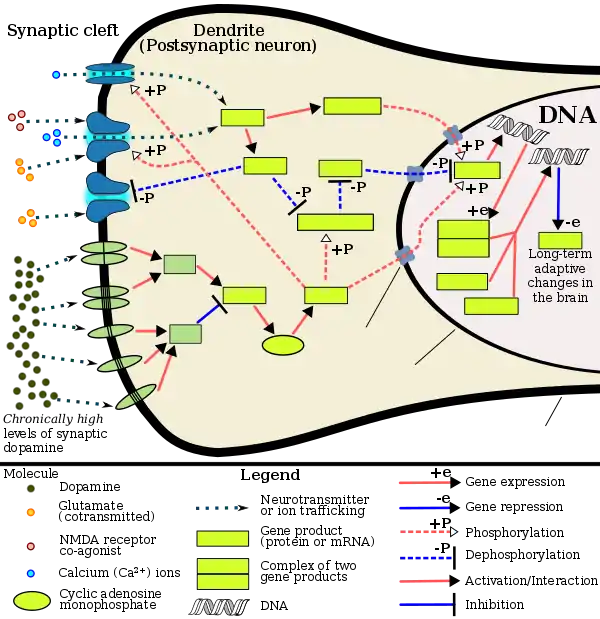

Current models of addiction from chronic drug use involve alterations in gene expression in certain parts of the brain, particularly the nucleus accumbens.[70][71] The most important transcription factors[note 4] that produce these alterations are ΔFosB, cAMP response element binding protein (CREB), and nuclear factor kappa B (NFκB).[71] ΔFosB plays a crucial role in the development of drug addictions, since its overexpression in D1-type medium spiny neurons in the nucleus accumbens is necessary and sufficient[note 5] for most of the behavioral and neural adaptations that arise from addiction.[61][71][73] Once ΔFosB is sufficiently overexpressed, it induces an addictive state that becomes increasingly more severe with further increases in ΔFosB expression.[61][73] It has been implicated in addictions to alcohol, cannabinoids, cocaine, methylphenidate, nicotine, opioids, phencyclidine, propofol, and substituted amphetamines, among others.[71][73][74][75][76]

ΔJunD, a transcription factor, and G9a, a histone methyltransferase enzyme, both directly oppose the induction of ΔFosB in the nucleus accumbens (i.e., they oppose increases in its expression).[61][71][77] Sufficiently overexpressing ΔJunD in the nucleus accumbens with viral vectors can completely block many of the neural and behavioral alterations seen in chronic drug use (i.e., the alterations mediated by ΔFosB).[71] ΔFosB also plays an important role in regulating behavioral responses to natural rewards, such as palatable food, sex, and exercise.[71][74][78] Since both natural rewards and addictive drugs induce expression of ΔFosB (i.e., they cause the brain to produce more of it), chronic acquisition of these rewards can result in a similar pathological state of addiction.[71][74] ΔFosB is the most significant factor involved in both amphetamine addiction and amphetamine-induced sex addictions, which are compulsive sexual behaviors that result from excessive sexual activity and amphetamine use.[note 6][74][79] These sex addictions (i.e., drug-induced compulsive sexual behaviors) are associated with a dopamine dysregulation syndrome which occurs in some patients taking dopaminergic drugs, such as amphetamine or methamphetamine.[74][78][79]